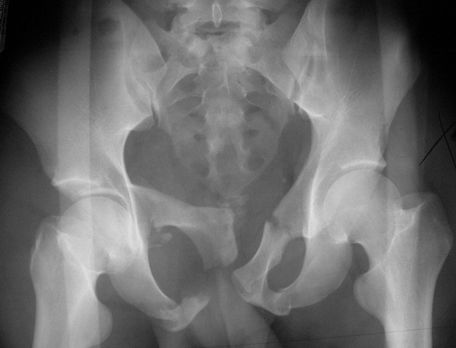

正常骨盆正位片

髋关节后脱位

髋关节前脱位

先天性髋脱位

常见髋关节测定线

骨盆骨折